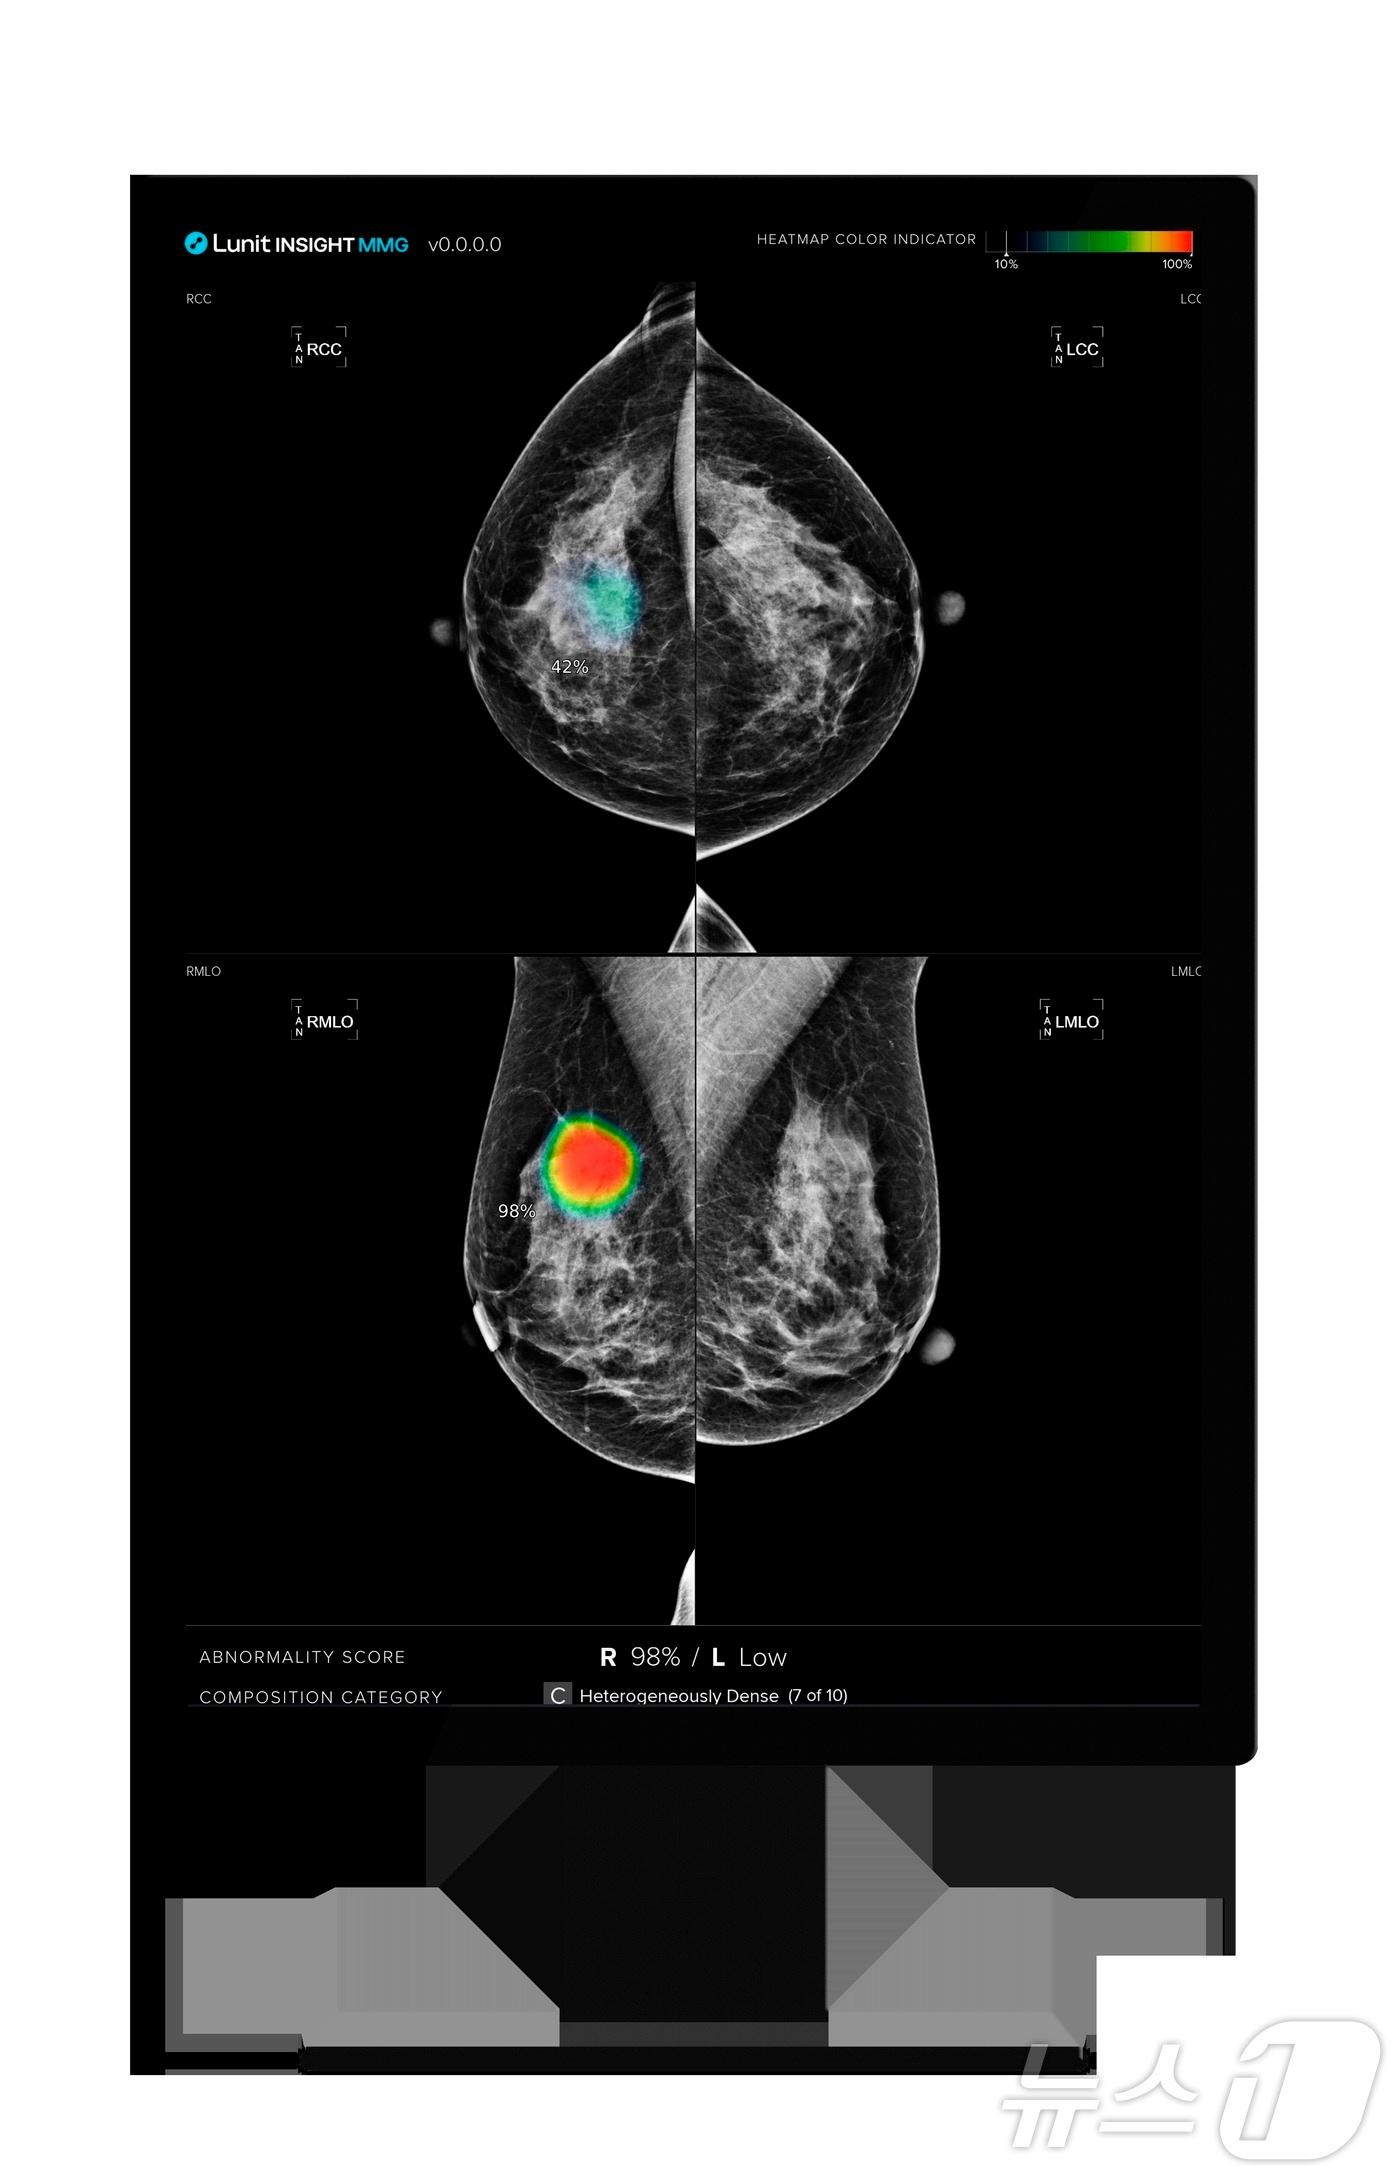

국가 검진 프로그램에 '루닛 인사이트 MMG' 5년간 활용"2년간 기술검증·본계약 체결로 중동 공략 가속"루닛 인사이트 MMG 활용 모습.(루닛 제공)/뉴스1관련 키워드루닛국가 유방암 검진루닛 인사이트 MMG의료 AI황진중 기자 산부인과 약으로 탄생한 '구내염' 치료제 '알보칠'[약전약후]휴온스바이오파마, 中서 'A형 보툴리눔 톡신' 승인…"현지 진출 본격화"관련 기사루닛, 스페인 발렌시아주 '국가 유방암 검진사업' 단독 수주루닛, 이탈리아 지방보건국 11곳에 AI 솔루션 공급…인구 14% 대상루닛, AI로 유방암 발견율 증가 입증…네이처 커뮤니케이션즈 게재루닛, ECR 2025서 유방촬영술 '이중 판독' 환경 AI 활용 연구결과 발표루닛, 작년 매출 전년比 2배 증가한 542억원 '역대 최대'